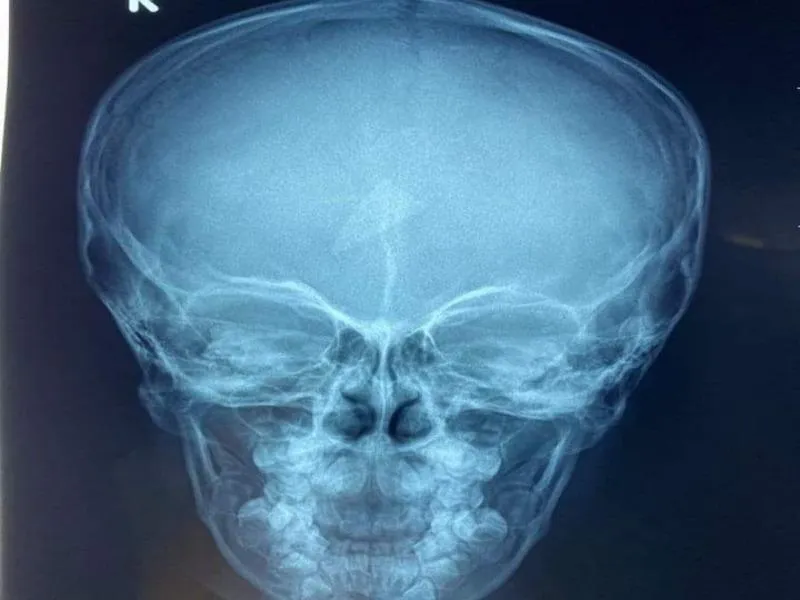

Ngày 4-6, thông tin từ Bệnh viện Sản - Nhi An Giang cho biết các bác sĩ vừa phẫu thuật lấy ra mảnh vỡ kính hình tam giác găm trong trán bé trai.

Bệnh nhi là bé NMH (4 tuổi, ngụ huyện Chợ Mới), nhập viện trong tình trạng ở trán bị sưng to, đau nhức. Người nhà cho biết, trước đó 2 ngày bé H. chơi đùa té vào tủ quần áo gây vỡ kính. Thấy bé chỉ bị trầy xước bên ngoài nên gia đình không đưa đi bệnh viện kiểm tra.

Mảnh kính hình tam giác găm ở giữa trán bé trai. Ảnh: BVCC

Tại bệnh viện, các bác sĩ kiểm tra tra thì phát hiện có dị vật nằm bên trán bé trai. Ngay sau đó, ê-kíp tiểu phẫu đã tiến hành gắp ra một mảnh vỡ kính hình tam giác sắc nhọn.